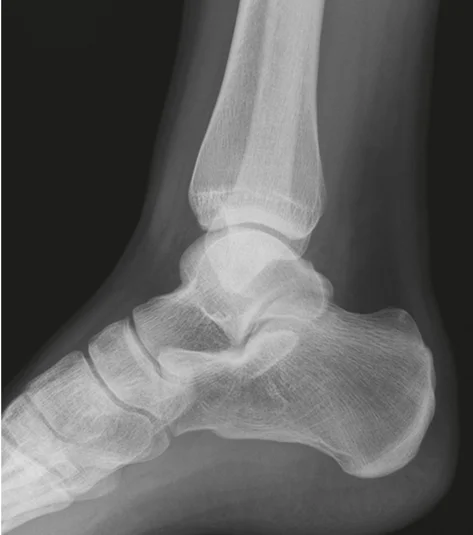

x-ray lat. view of ankle joint

- The image presents two X-ray views of an ankle joint.

- The left image is a plain X-ray.

- The right image is a labeled version of the same X-ray.

Labeled Components:

- Bones:

- tibia

- fibula

- talus

- navicular

- cuboid

- calcaneus

- MT5 (Fifth Metatarsal)

- Other Structures:

- achilles tendon

- Kagerâs Fat Pad

- Joints:

- subtalar joint

- Other:

- mal. tertius